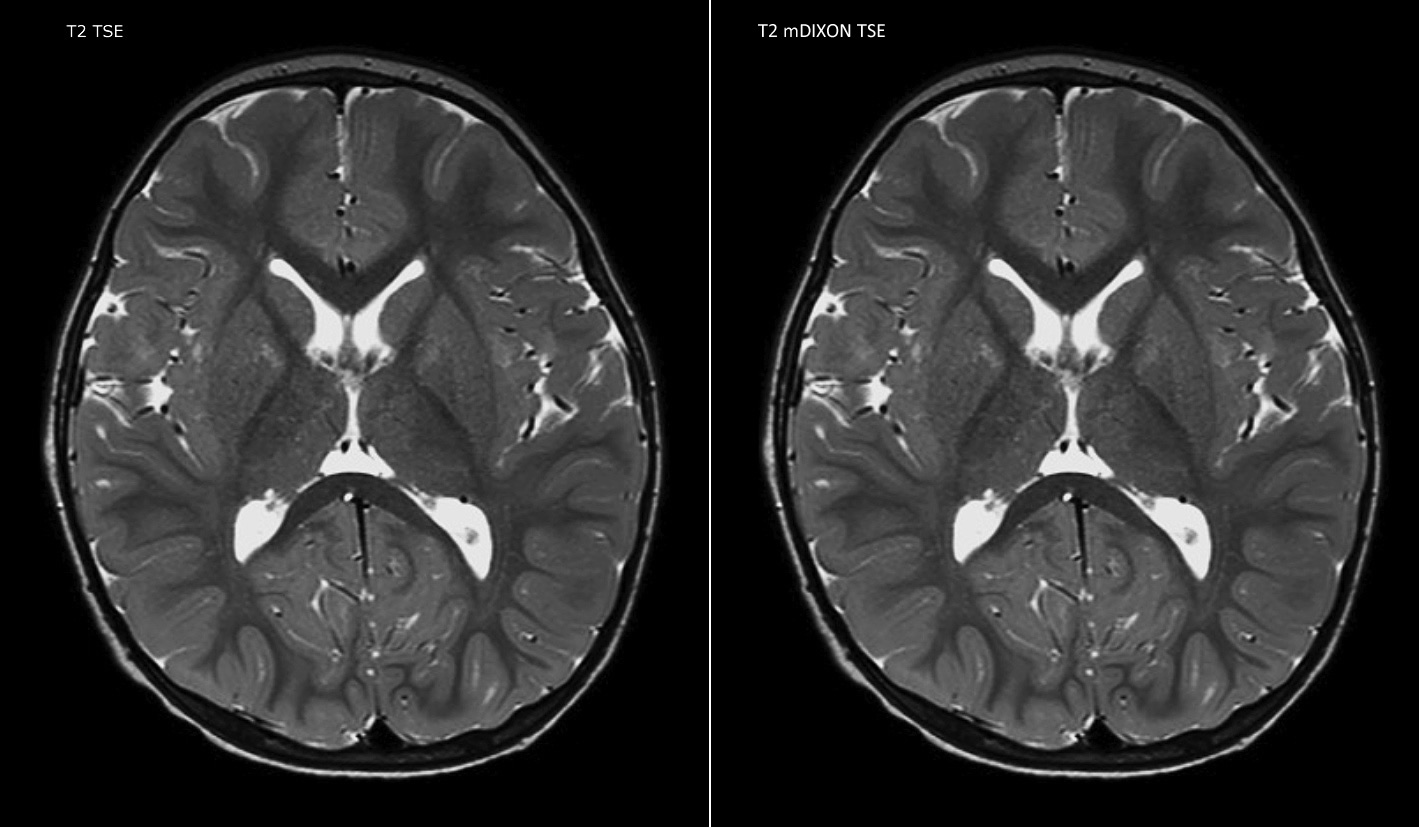

Philips mDIXON TSE is a two-point DIXON technique that separates water and fat signals, for time-efficient fat-free imaging, even in challenging neuro anatomy.

“mDIXON TSE has been one of the most significant improvements in imaging sequences that we have utilized to date at PCH,” says Dr. Miller. “Its multi-parametric acquisition allows us to obtain fat suppressed images and equivalent non-fat suppressed T2 images all in the same sequence. In addition, prior methods of fat suppression could be artifactually corrupted by poor patient anatomy or poor operator application, but with mDIXON we now have a robust and reliable method of fat suppression.”

Fat saturation is historically challenging at the ends of fields of view, especially in total spine imaging and in difficult patient anatomy such as the lower regions of the neck. “Due to the unique fat suppression capabilities of mDIXON, however, these challenges no long apply,” says Dr. Miller. “We routinely obtain homogeneous fat suppression under virtually all conditions. It has also led to some efficiencies by not having to repeat sequences because of that technical failure.”

“mDIXON TSE is most useful in patients with lesions or abnormalities in the soft tissues such as the face and neck, and for patients with contrast enhancing abnormalities that are mostly visible with fat suppression,” says Dr. Miller. “All our spine imaging now routinely contains mDIXON water-only T2 images, and this allows us to identify pathology that may be obscured by non-fat suppressed imaging such as injuries of the bone. And it’s not necessary to obtain additional standard TSE T2 images because the in-phase mDIXON images are equivalent to standard TSE T2 images.”